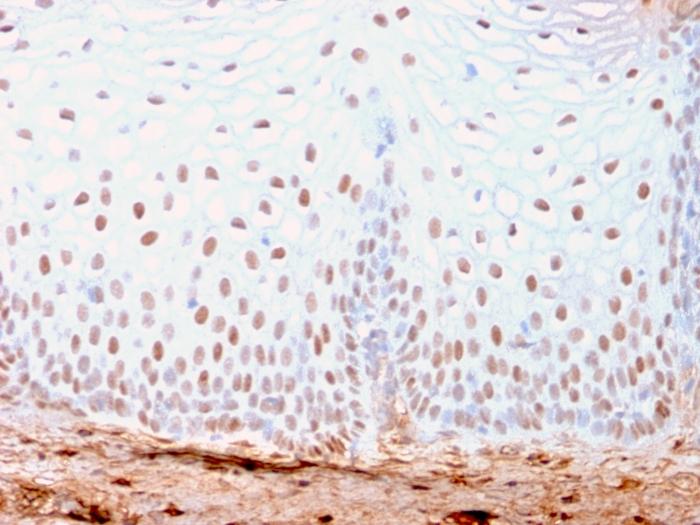

SOX2 is required for stem cell maintenance in the central nervous system, and it also regulates gene expression in the stomach. SOX2 is necessary for regulating multiple transcription factors that affect Oct 3/4 expression. An essential function of SOX2 is to stabilize embryonic stem cells in a pluripotent state by maintaining the requisite level of Oct 3/4 expression. Reportedly, SOX2 is associated with aggressive phenotypes of breast, head and neck, gastric, colorectal, bladder, and small cell lung cancers. However, SOX2 is expressed in a high percentage of lung squamous cell carcinomas and has been shown to be an independent favorable prognostic marker. Primary antibodies are available purified, or with a selection of fluorescent CF® Dyes and other labels. CF® Dyes offer exceptional brightness and photostability. Note: Conjugates of blue fluorescent dyes like CF®405S and CF®405M are not recommended for detecting low abundance targets, because blue dyes have lower fluorescence and can give higher non-specific background than other dye colors.

A549, NCCIT cells. Lung or Cervical carcinoma.

Nucleus

IHC, FFPE (verified)

IHC (FFPE) (verified)